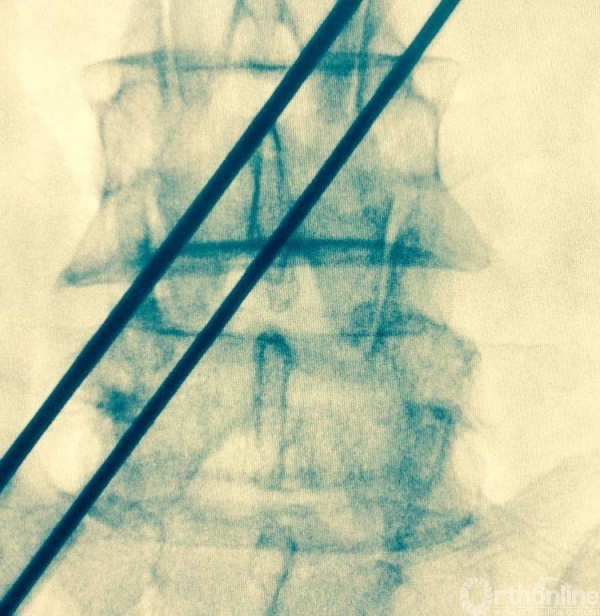

消毒前,给予椎间隙定位

按照定位标志,画出L4-L5椎弓根位置,为零透视下椎管减压做准备

术前透视标记出棘突椎板关节突关节、椎弓根、横突复合体螺钉进钉路线的正位透视片